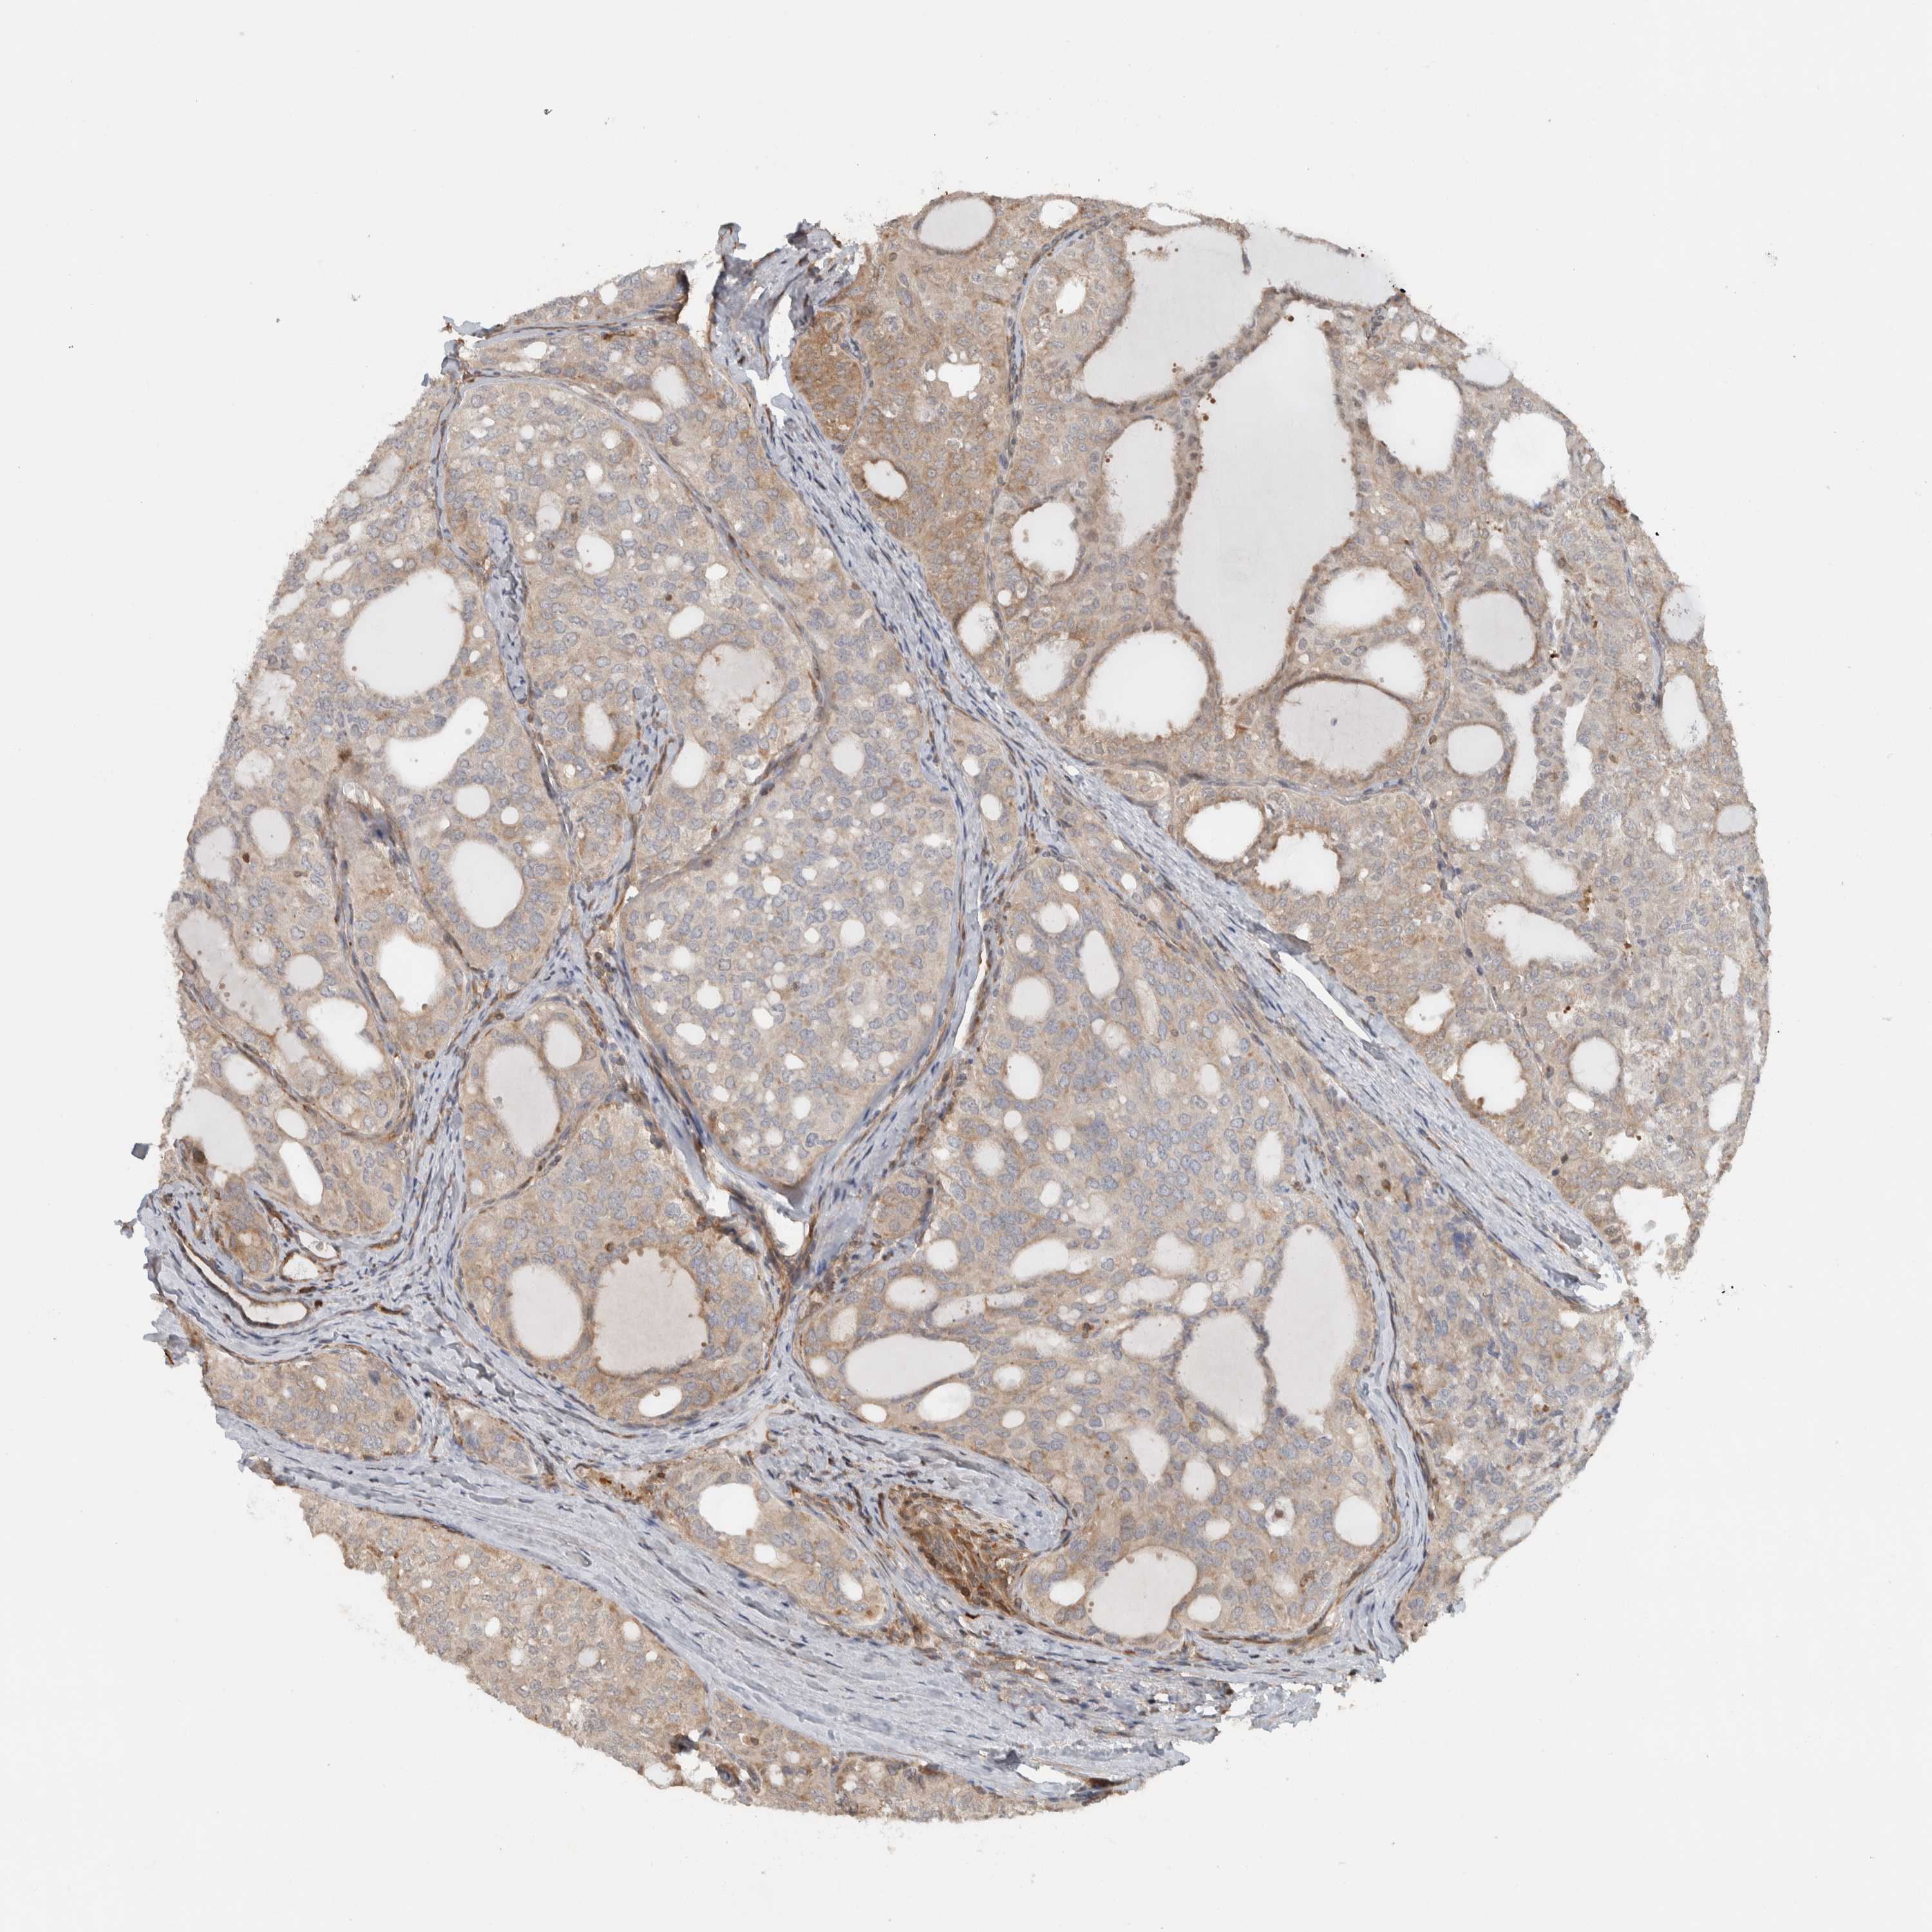

THYROID CANCER - Protein expressioni

A mouse-over function shows sample information and annotation data. Click on an image to view it in a full screen mode. Samples can be filtered based on level of antibody staining by selecting one or several of the following categories: high, medium, low and not detected. The assay and annotation is described here.

Note that samples used for immunohistochemistry by the Human Protein Atlas do not correspond to samples in the TCGA dataset.

Antibody stainingi

Antibody staining in the annotated cell types in the current human tissue is reported as not detected, low, medium, or high, based on conventional immunohistochemistry profiling in selected tissues. This score is based on the combination of the staining intensity and fraction of stained cells.

Each image is clickable and will lead to virtual microscopy that enables deeper exploration of all samples and also displays staining intensity scores, fraction scores and subcellular localization as well as patient and tissue information for each sample.

Antibody HPA023319

Antibody HPA023320

Antibody HPA023321

Antibody HPA023325

Papillary adenocarcinoma, NOS

Follicular adenoma carcinoma, NOS